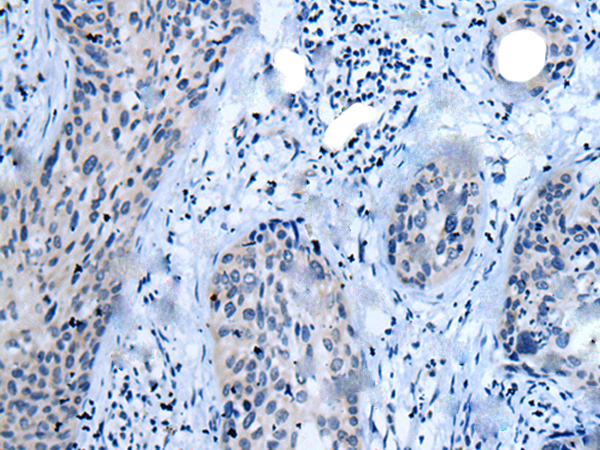

ELISA, IHC |

IHC positive control: |

Human cervical cancer |

IHC Recommend dilution: |

10-50 |